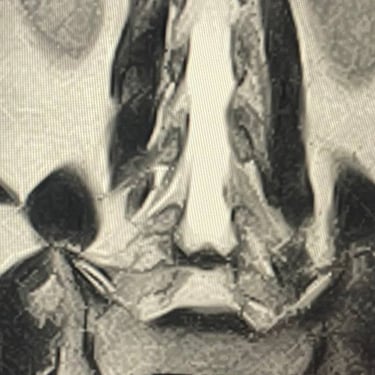

3 level cervical herniated discs treated by Discogel injection

"Discogel injection for the treatment of cervical herniated discs

Patient's image after injection and Several years post-injection, the patient's mobility issues and pains have disappeared